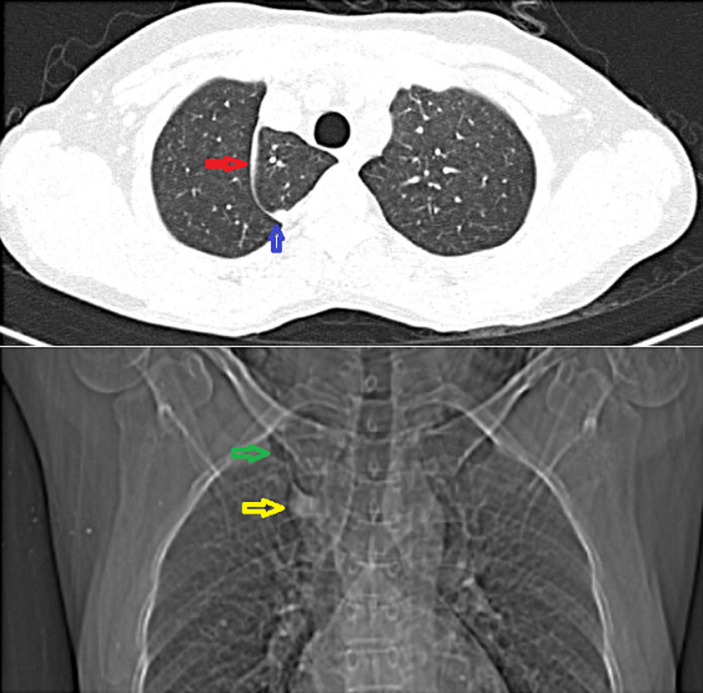

奇叶-罕见的解剖变异。

Azygos lobe-a rare anatomical variant.